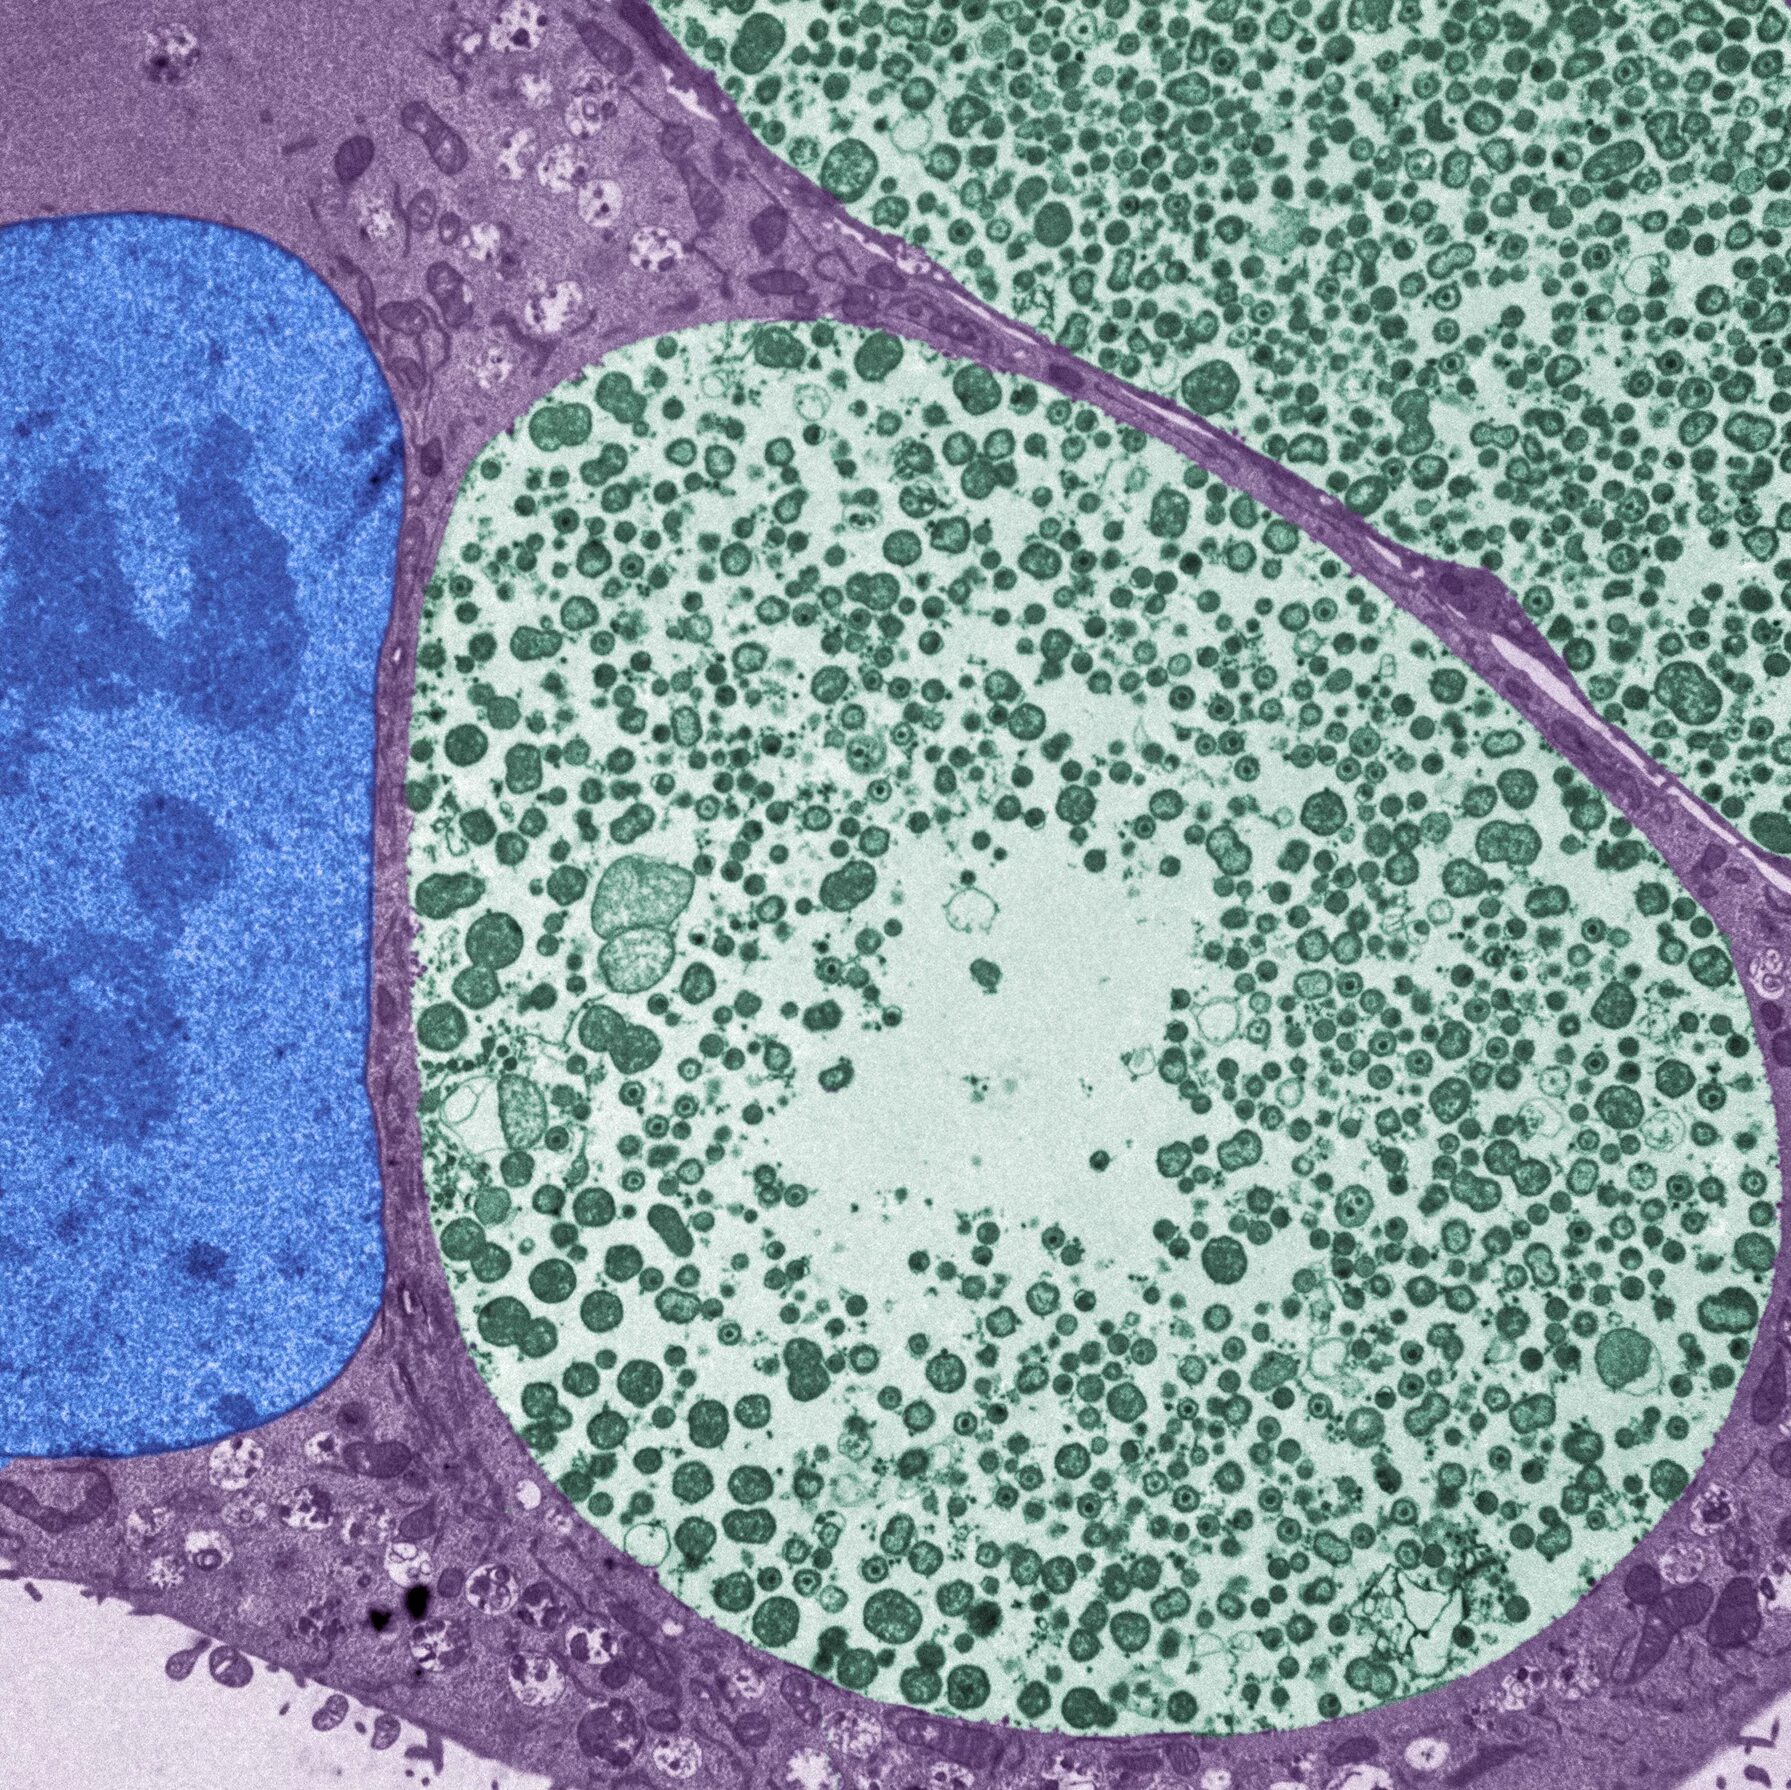

Хламидии под микроскопом